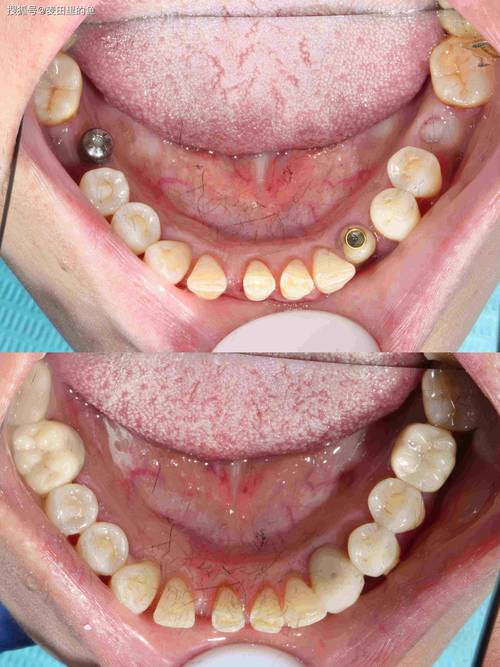

传统种牙需经历“拔牙-等待3-6个月-植骨-再等待3个月-戴牙”的漫长周期,而微创即刻种植技术通过“不翻瓣”或“小切口”手术,结合数字化导板,实现“即拔即种”——在拔除患牙的同时植入种植体,甚至当天安装临时牙冠,实现“当天种牙、当天用牙”。

该技术的核心在于“微创”与“即刻”:微创手术通过牙龈微小切口(约3-5毫米)植入种植体,不翻开牙龈瓣,减少对软组织的损伤,术后疼痛感轻、恢复快;即刻种植则依托数字化精准定位,确保种植体初期稳定性(骨量需充足),结合生物活性材料(如PRF富血小板纤维蛋白),促进拔牙窝与种植体周围骨组织同步再生,即刻种植对患者的骨量、牙槽骨密度及全身健康状况要求较高,需医生严格评估适应症。